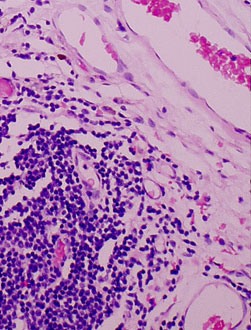

Cases